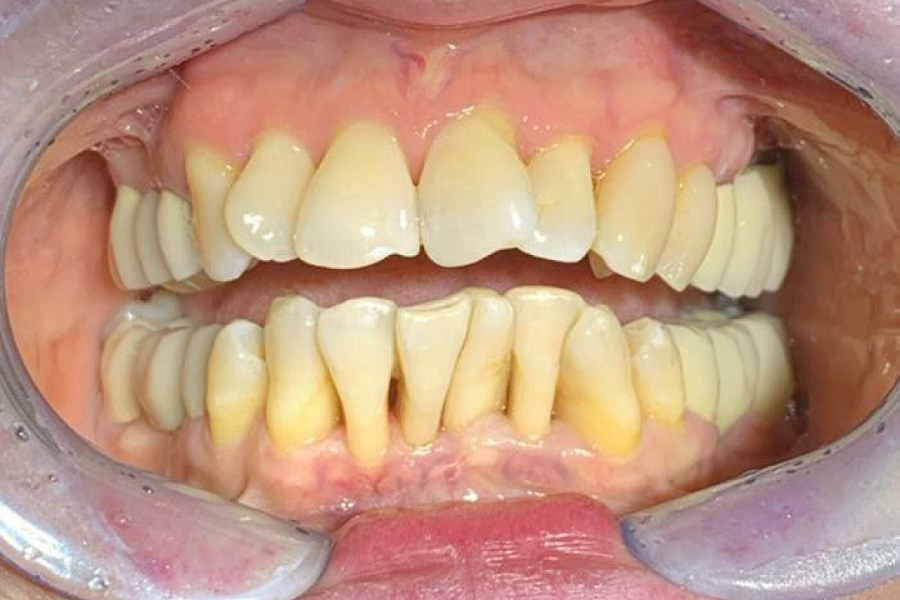

Выраженный пародонтит и дефицит костной ткани, сильная скученность зубов.

К сожалению, ортодонтическое лечение этой пациентки не может быть проведено, потому что зубы слишком крупные и очень большой дефицит костной ткани. Поэтому перемещение зубов ортодонтическими конструкциями приведет к их потере. Поэтому наша команда предложила протезирование верхнего зубного ряда и создание эстетических реставраций, которые бы не только исправили внешний вид зубов, но и дополнительно создали стабильность зубного ряда. На нижней челюсти мы провели чистку, полировку и шинирование зубов.